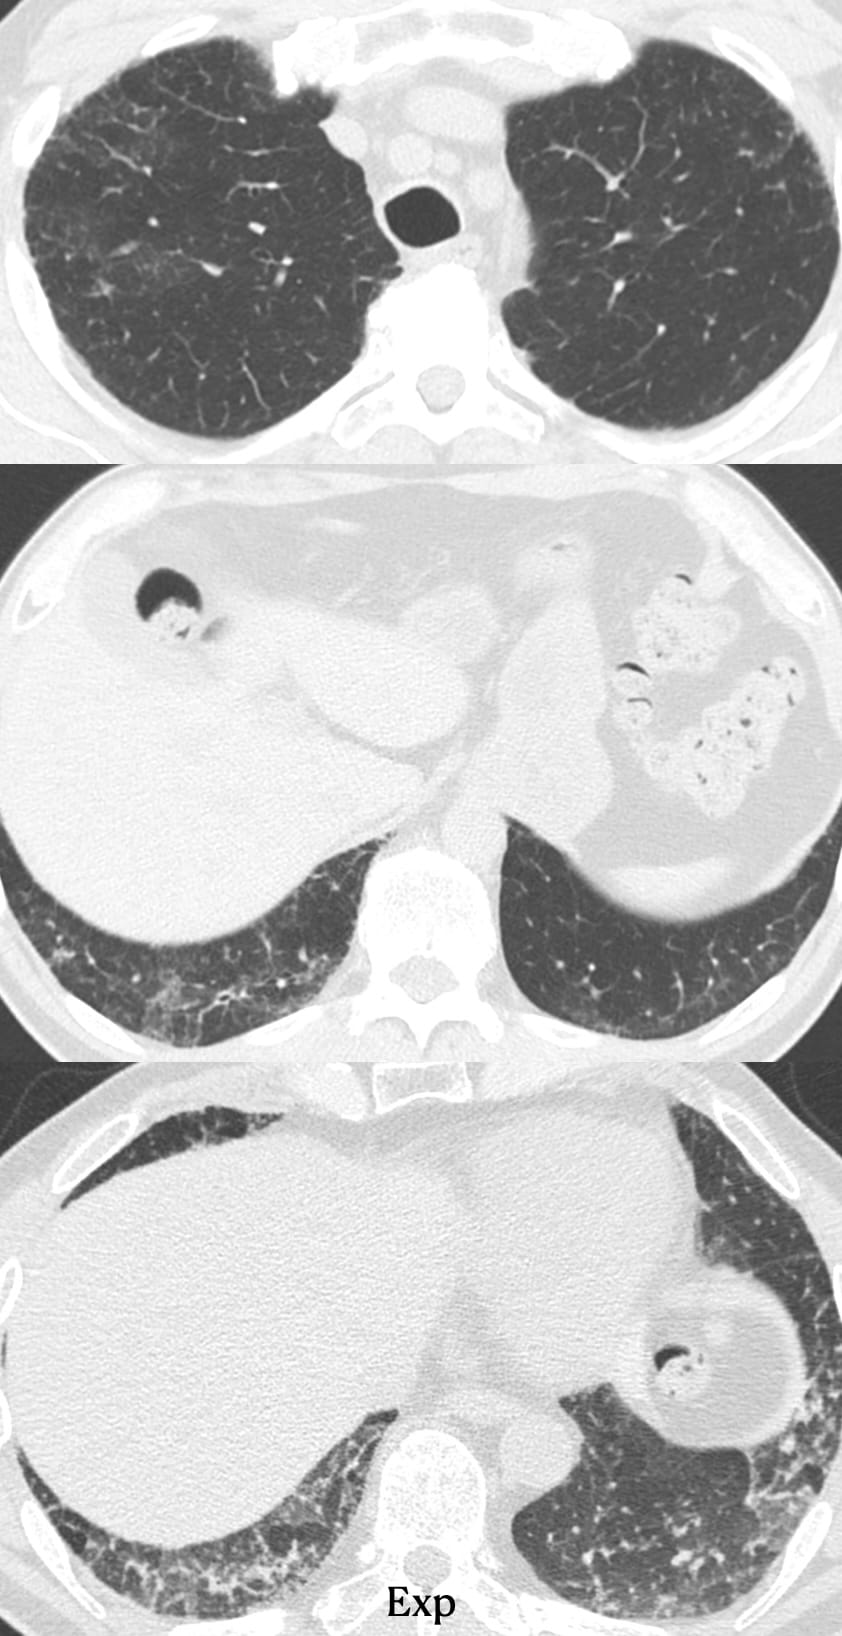

- Usual Interstitial Pneumonia